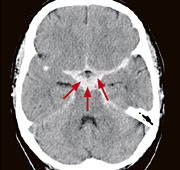

Abb. 1

Akut aufgetretener, heftigster Kopfschmerz. Das Computertomogramm zeigt eine Einblutung in den Liquorraum (SAB, Pfeile) nach Einriss eines Aneurysmas (krankhafte Gefässaussackung).